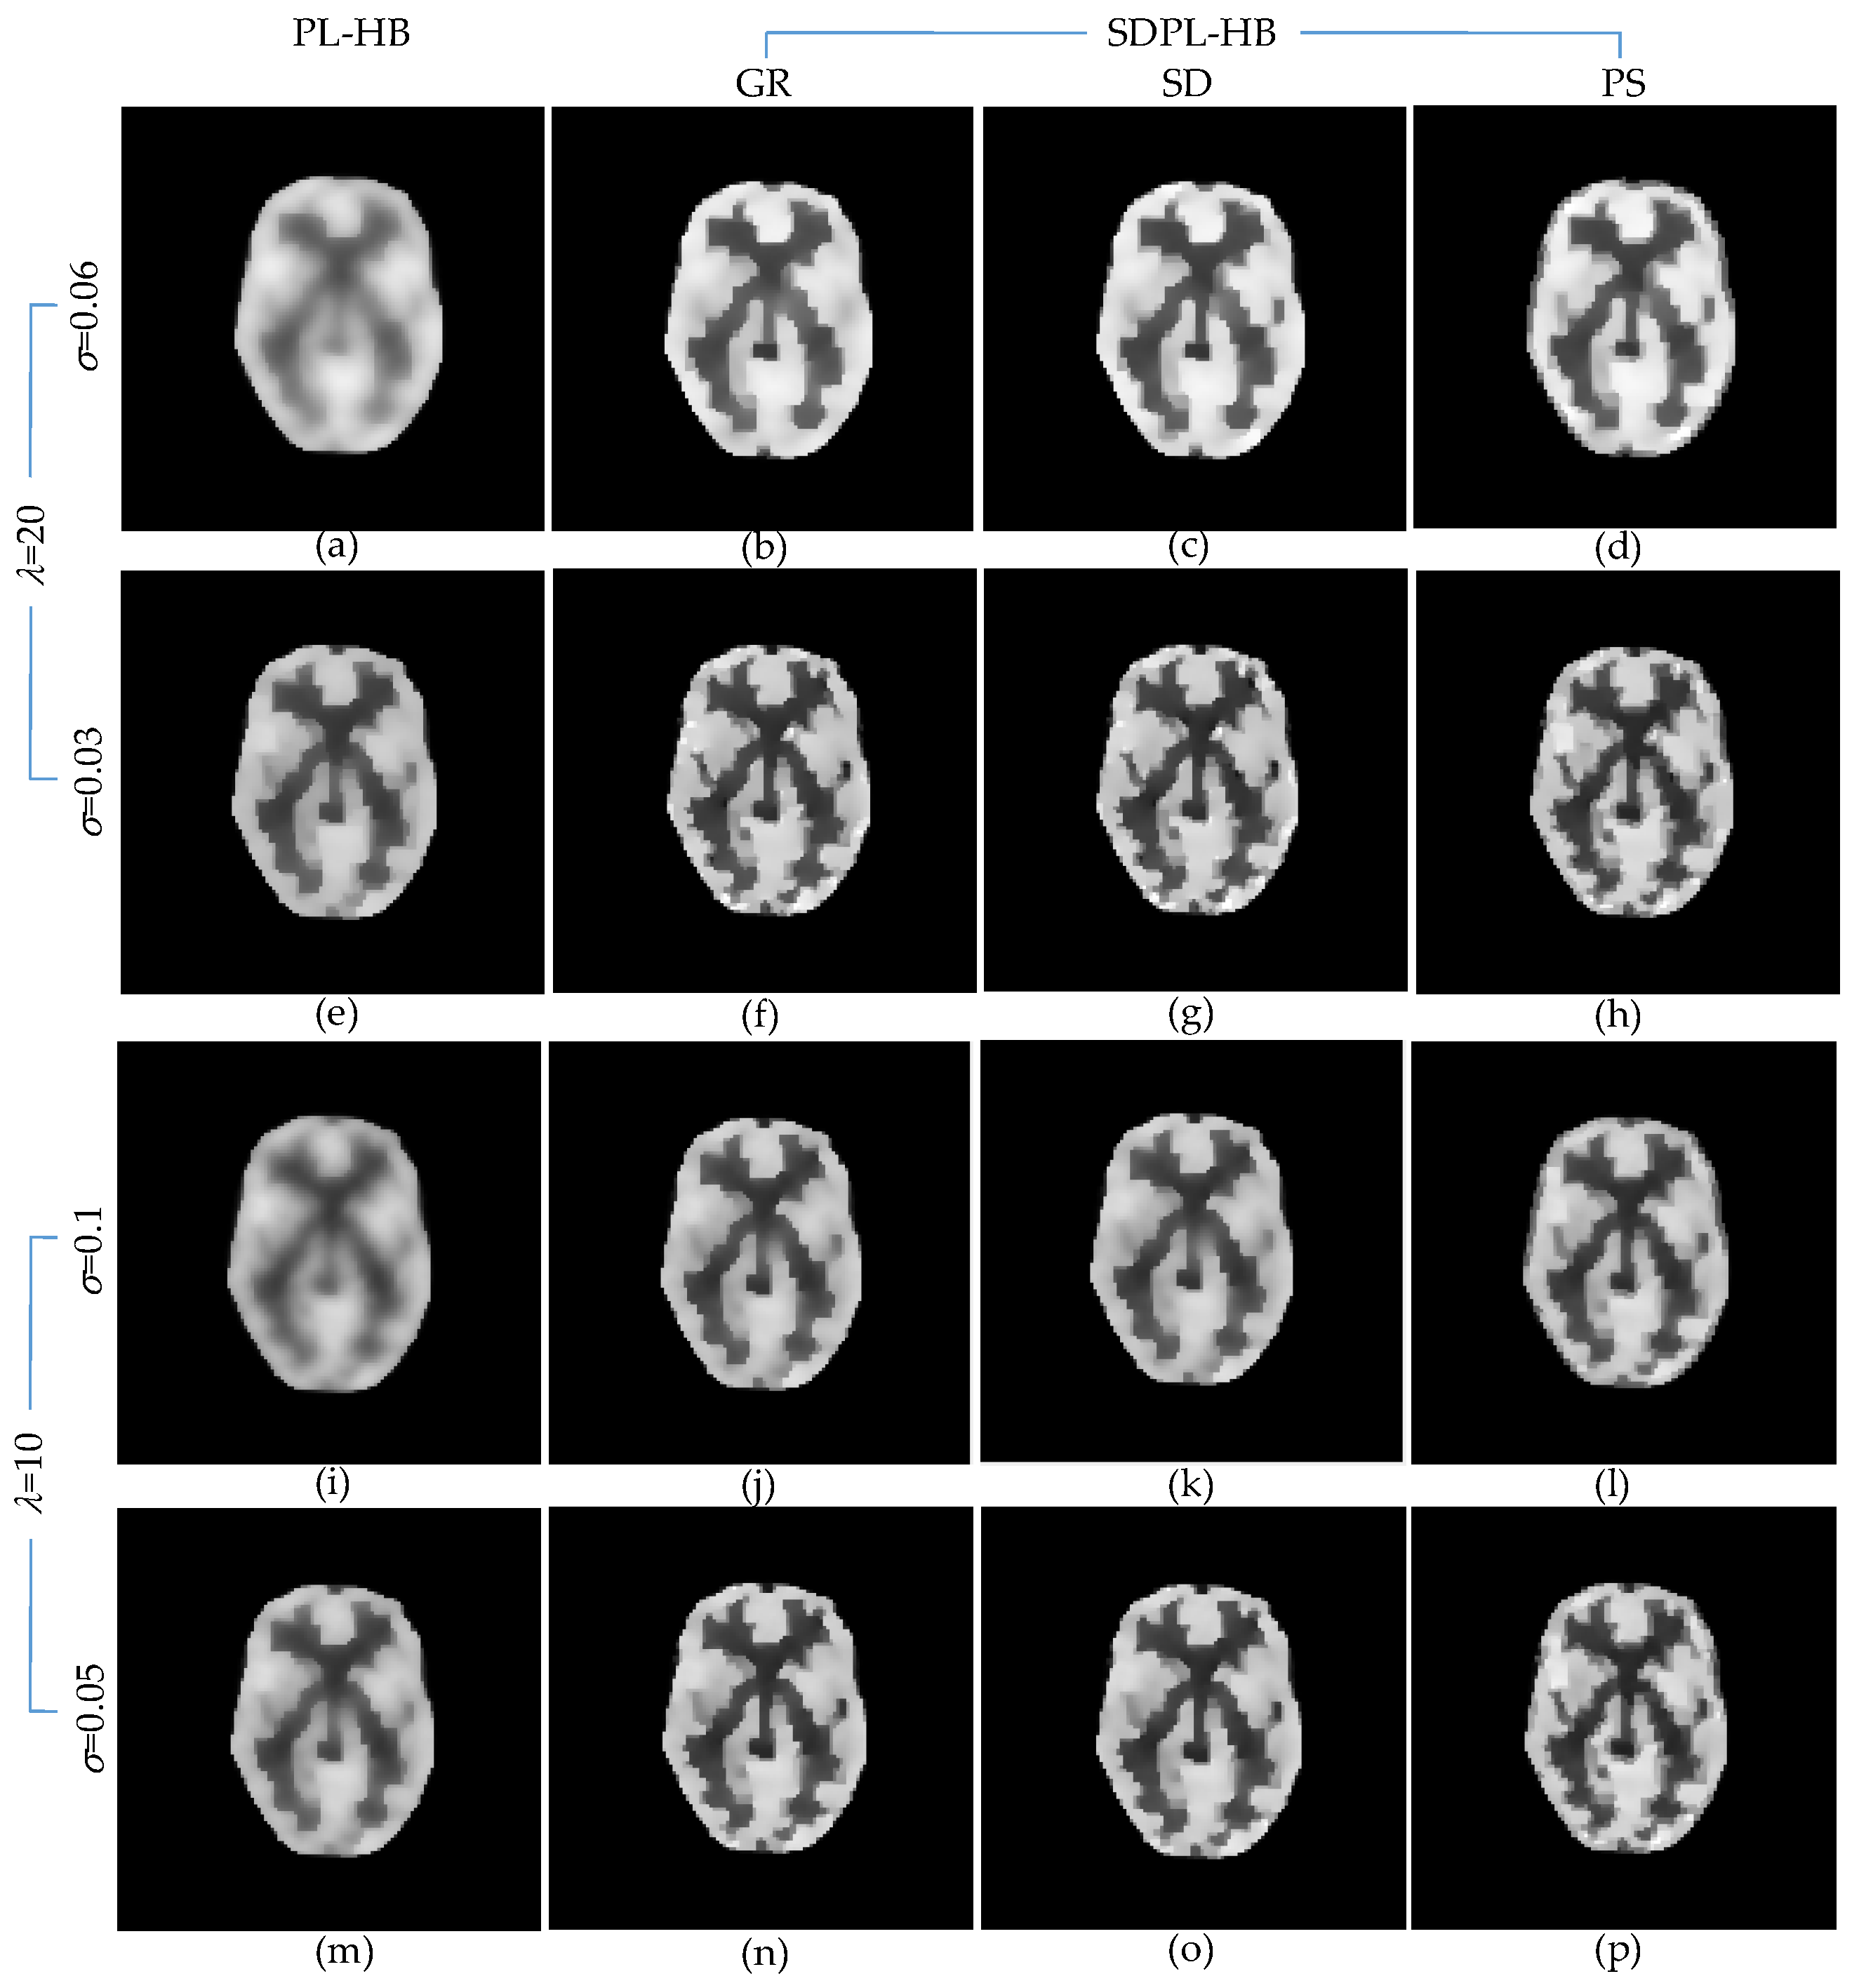

| IQA Metrics | PL-HB | SDPL-HB | |||

|---|---|---|---|---|---|

| GR | SD | PS | |||

| λ = 20 σ = 0.06 | PSNR(dB) | 13.857 | 15.798 | 16.239 | 15.421 |

| MSSIM | 0.823 | 0.880 | 0.889 | 0.868 | |

| VIF | 0.401 | 0.574 | 0.611 | 0.567 | |

| MAE | 0.091 | 0.064 | 0.059 | 0.065 | |

| RMSE | 0.203 | 0.162 | 0.154 | 0.169 | |

| MPE | 37.018 | 29.605 | 28.142 | 30.920 | |

| λ = 20 σ = 0.03 | PSNR(dB) | 15.838 | 17.277 | 17.353 | 17.134 |

| SSIM | 0.880 | 0.914 | 0.916 | 0.912 | |

| VIF | 0.569 | 0.697 | 0.710 | 0.691 | |

| MAE | 0.064 | 0.049 | 0.049 | 0.050 | |

| RMSE | 0.162 | 0.137 | 0.136 | 0.139 | |

| MPE | 29.469 | 24.971 | 24.755 | 25.386 | |

| λ = 10 σ = 0.1 | PSNR(dB) | 14.387 | 16.176 | 16.149 | 15.974 |

| SSIM | 0.837 | 0.888 | 0.887 | 0.883 | |

| VIF | 0.450 | 0.606 | 0.607 | 0.615 | |

| MAE | 0.083 | 0.059 | 0.059 | 0.059 | |

| RMSE | 0.191 | 0.155 | 0.156 | 0.159 | |

| MPE | 34.826 | 28.346 | 28.434 | 29.011 | |

| λ = 10 σ = 0.05 | PSNR(dB) | 15.564 | 17.086 | 17.086 | 16.938 |

| SSIM | 0.872 | 0.909 | 0.909 | 0.908 | |

| VIF | 0.550 | 0.684 | 0.689 | 0.688 | |

| MAE | 0.067 | 0.050 | 0.050 | 0.051 | |

| RMSE | 0.167 | 0.140 | 0.140 | 0.142 | |

| MPE | 30.412 | 25.526 | 25.527 | 25.963 | |